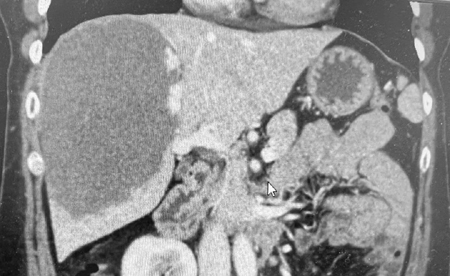

53岁的王女士平时一直身体很好,这次是来北京看儿子的。临近年关,孩子带着王女士做体检,超声检查偶然发现肝脏长了个13cm的肿物,进一步增强CT确诊为巨大肝血管瘤。

在心脏问题得到处理后,普外科重新将王女士收入院。术前评估发现王女士血管瘤与右肝的肝蒂和肝静脉关系密切,实施右半肝切除是相对容易的手术方式,但右半肝切除会损失20%左右的正常肝组织。在对影像进行详细研判的基础上,结合既往的肝脏手术经验,高鹏骥主任团队选择了难度相对更大但患者获益更多的血管瘤剥除手术。2022年1月6日,在麻醉团队和手术室护理团队的密切配合下,普外科成功为王女士实施了腹腔镜下巨大血管瘤剥除手术,术后在监护室短暂过渡后返回普通病房, 1周后王女士就完全康复出院了。